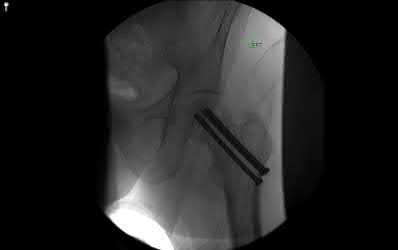

Illustration A shows a heterotrophic non-union of the tibia after intramedullary nailing. The patient was treated with exchange nailing with a larger nail. On the right shows a 4 month post-op radiograph after exchange nailing showing osseous union at the fracture site.